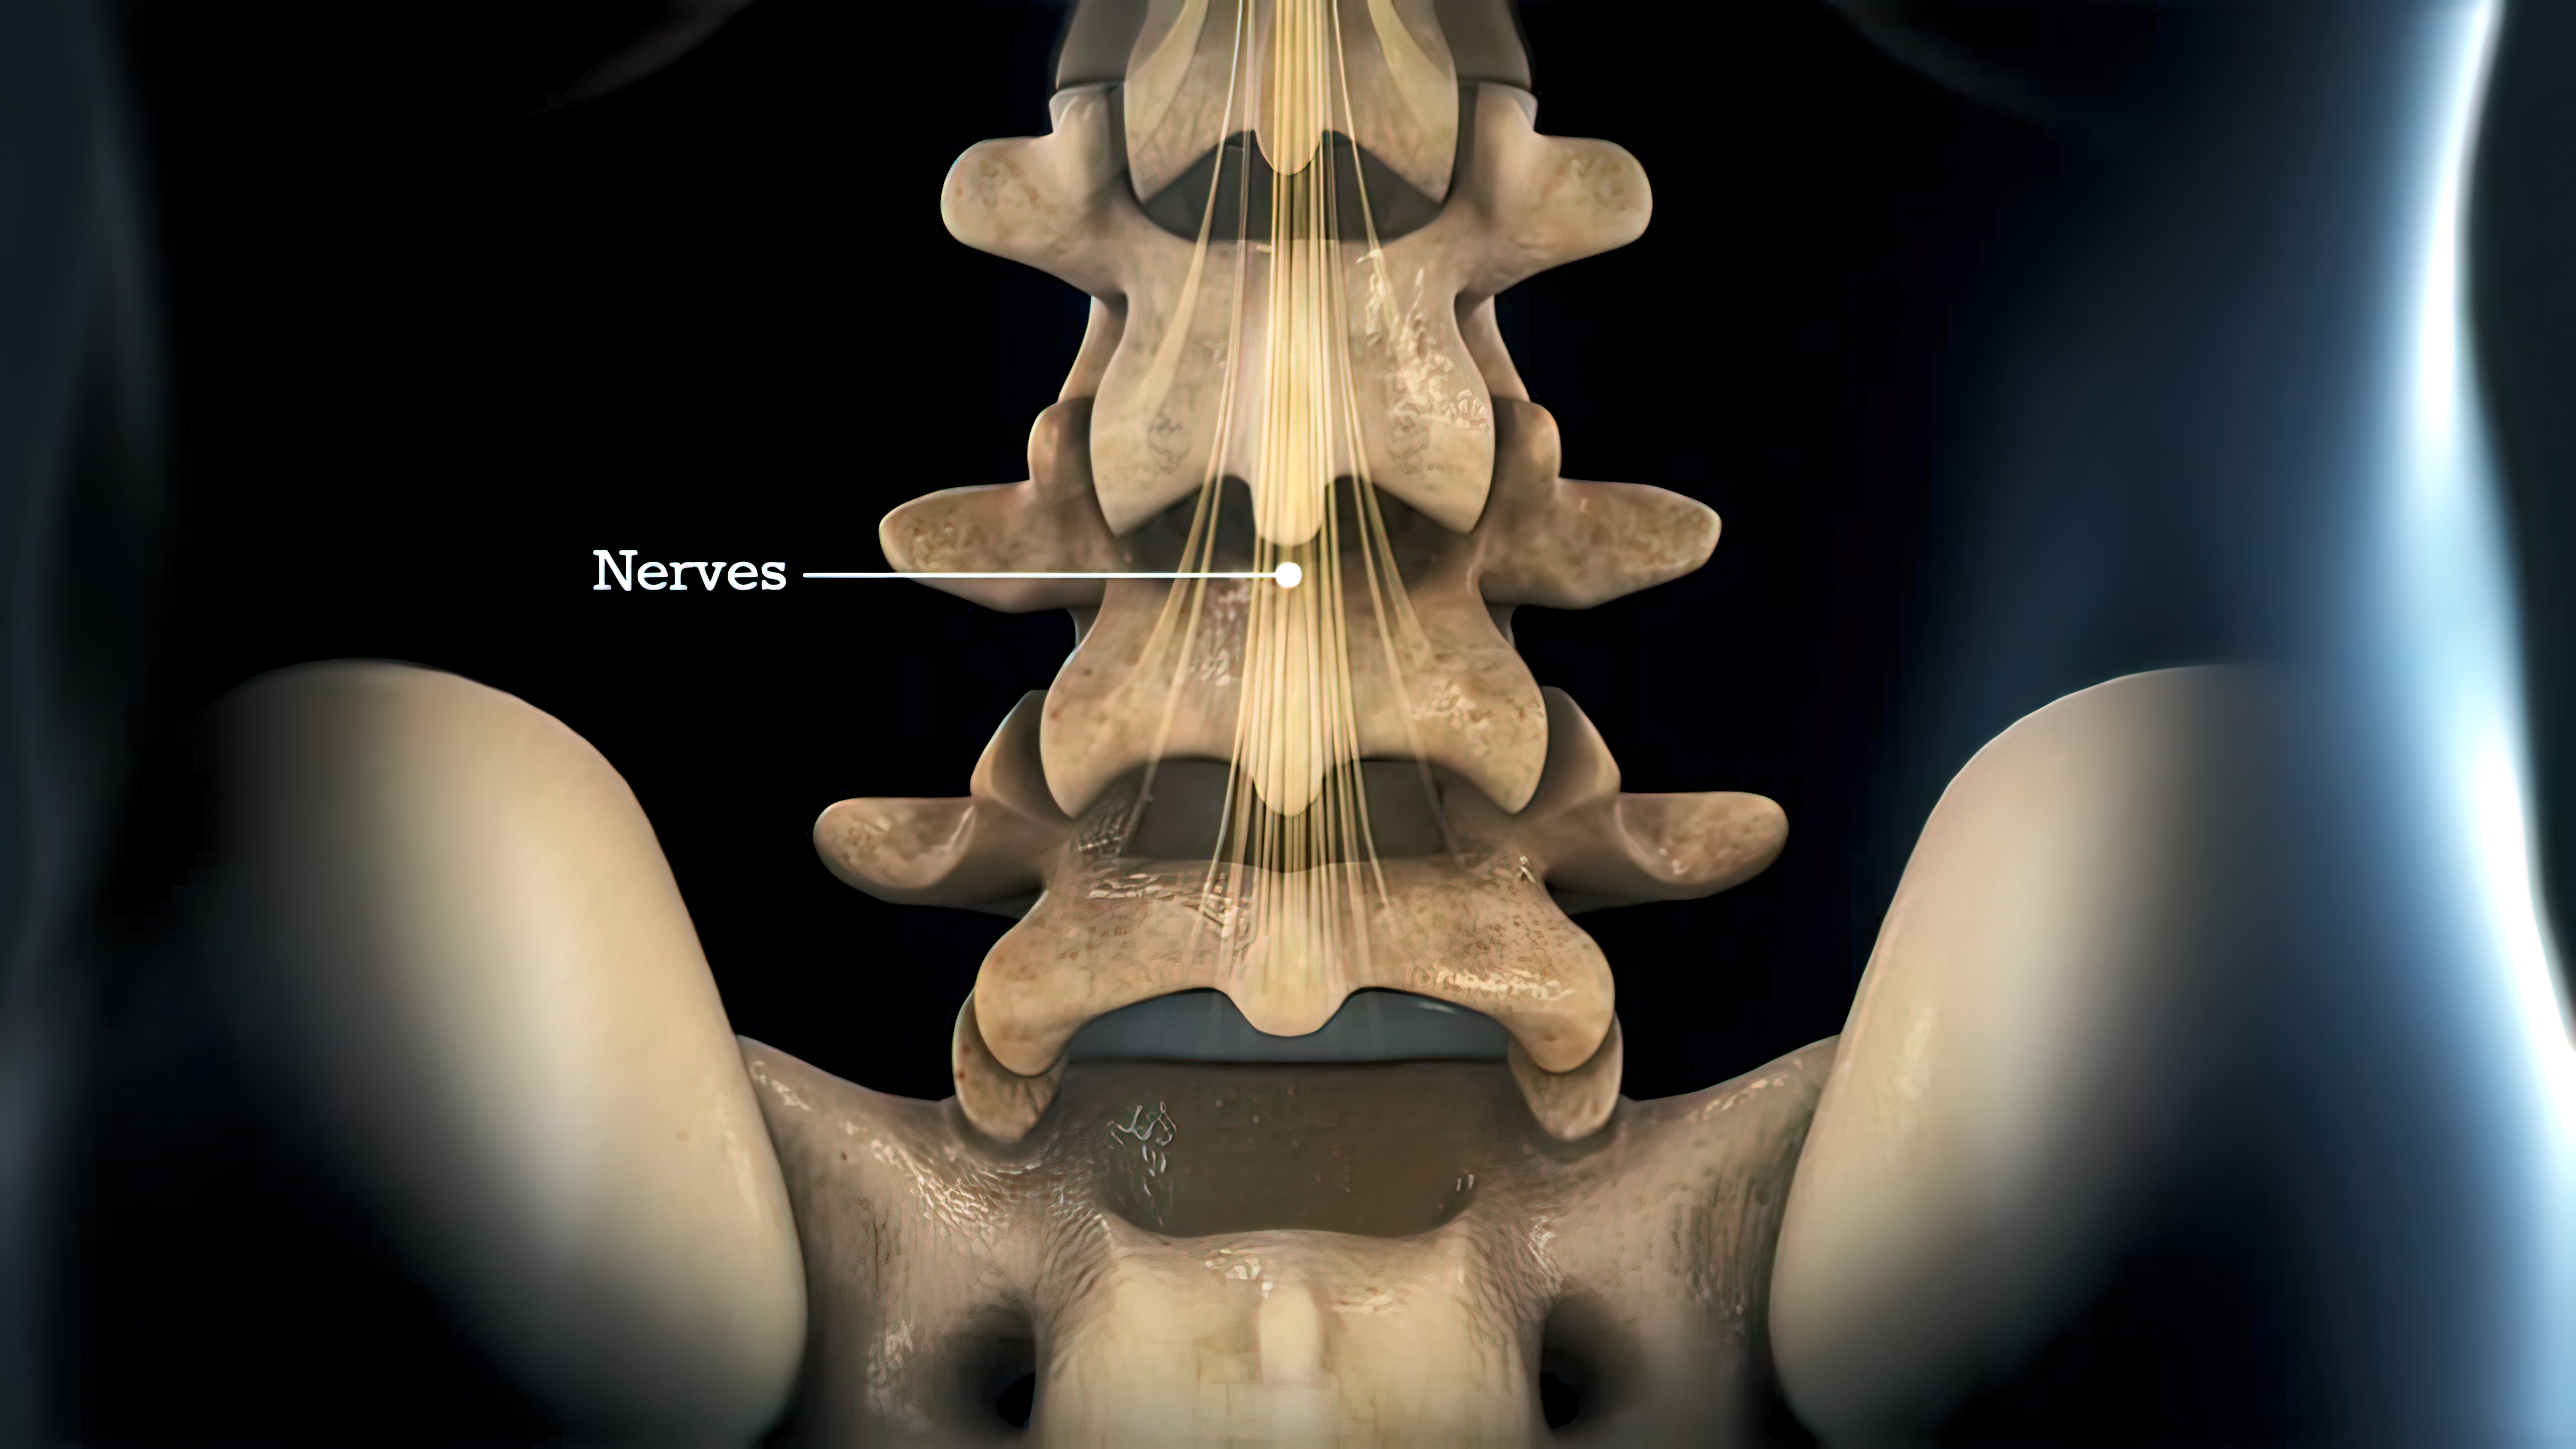

高清动图:UBE手术步骤演示!